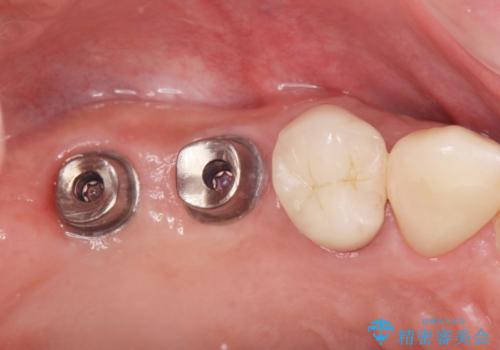

人工歯根であるインプラントを埋入することで奥歯でまたしっかりと噛める咬合機能を回復します。

- 88万円(インプラント×2・仮歯×2・チタンカスタムアバットメント×2・ジルコニアクラウン×2)費用は治療当時の料金となります